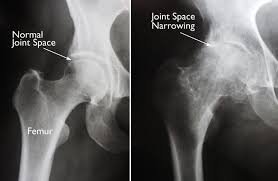

Hip replacement surgery, also known as hip arthroplasty, is a medical procedure in which a damaged or diseased hip joint is replaced with an artificial joint (called a prosthesis). This surgery is commonly performed to relieve pain, improve mobility, and restore function in individuals with severe hip joint damage.

Hip replacement surgery is typically recommended when the hip joint becomes damaged or worn out, causing chronic pain, stiffness, and loss of function. The goal of the procedure is to relieve pain, restore mobility, and improve the overall quality of life when non-surgical treatments are no longer effective. Hip replacement surgery is typically recommended when the hip joint becomes damaged or worn out, causing chronic pain, stiffness, and loss of function. The goal of the procedure is to relieve pain, restore mobility, and improve the overall quality of life when non-surgical treatments are no longer effective.